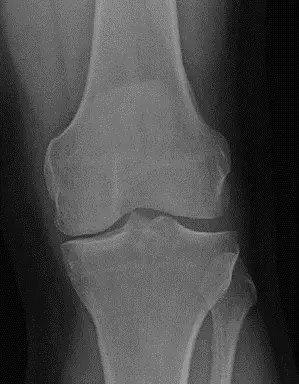

- الأشعة السينية العادية (Plain Radiographs):

- الوضعيات الواقفة (Standing AP, Lateral, Merchant views): هي الأهم، حيث تظهر المفصل تحت تأثير الوزن. تكشف عن:

- ضيق المسافة المفصلية (Joint Space Narrowing): علامة رئيسية لتآكل الغضروف. في حالة المريض، كان هناك ضيق شديد وشبه كامل في الجزء الإنسي من الركبة اليمنى.

- النتوءات العظمية (Osteophytes): نمو عظمي زائد حول المفصل.

- تصلب العظم تحت الغضروف (Subchondral Sclerosis): زيادة كثافة العظم تحت الغضروف المتآكل.

- التكيسات تحت الغضروف (Subchondral Cysts): جيوب مملوءة بالسوائل داخل العظم.

- التشوه (Deformity): مثل التقوس الشديد (Varus Deformity) الذي كان واضحاً في الركبة اليمنى للمريض.

- تصنيف كيلغرين-لورانس (Kellgren-Lawrence Classification): يستخدم لتقييم شدة الخشونة بناءً على الأشعة السينية. تتراوح الدرجات من 0 (طبيعي) إلى IV (شديد). في حالة المريض، كانت الركبة اليمنى من الدرجة IV، مما يشير إلى خشونة شديدة جداً.